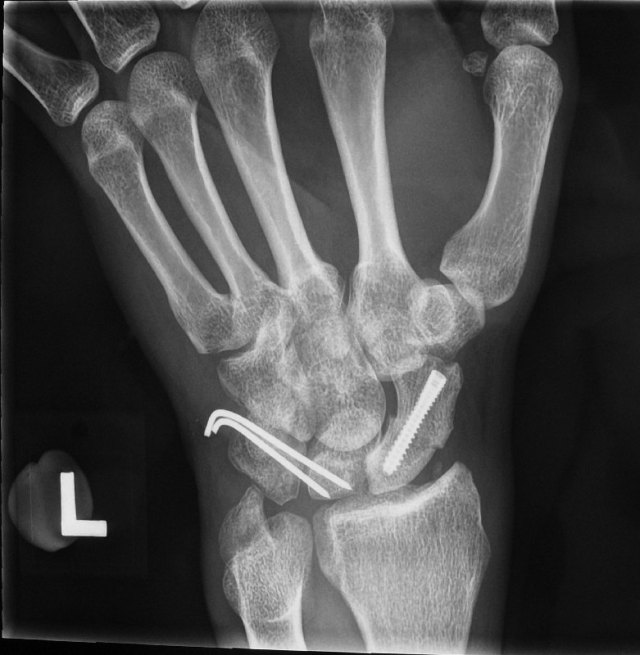

X-rays of his left wrist showed a fracture through the scaphoid bone of the wrist together with dislocation of the lunate bone. The diagnosis was a trans-scaphoid peri-lunate fracture dislocation.

This is how the x-rays looked like after the surgery: